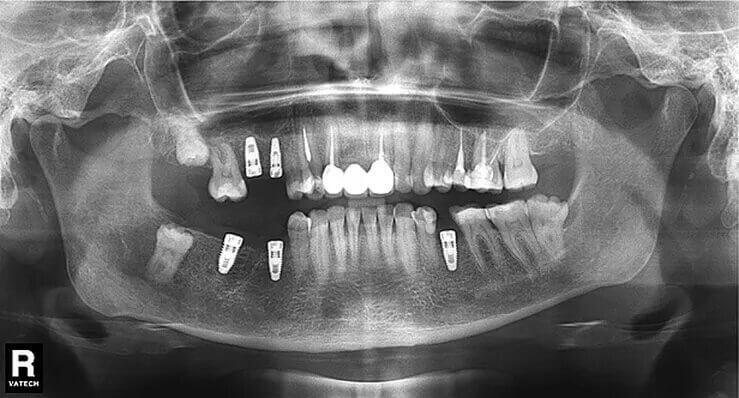

Рентген имплантов Alpha Bio: диагностика и качество